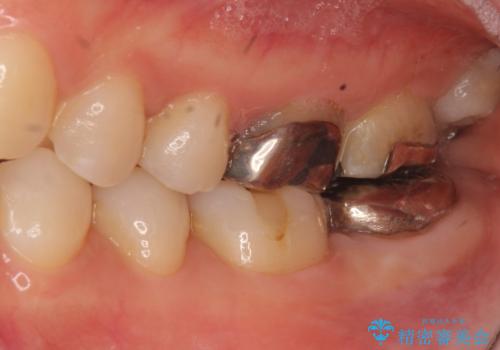

- 昔何回か根管治療した奥歯が膿んでいていて痛みがあることを主訴に来院された患者様です。

精査したところ、左下の奥歯にはひびが入っていて、保存不可能な状態でした。

義歯・インプラント・親知らずの移植の選択肢を提案したところ、移植をご希望されました。

割れている奥歯を抜去後左上の機能していない親知らずを移植し、生着したのち根管治療・補綴を行いました。